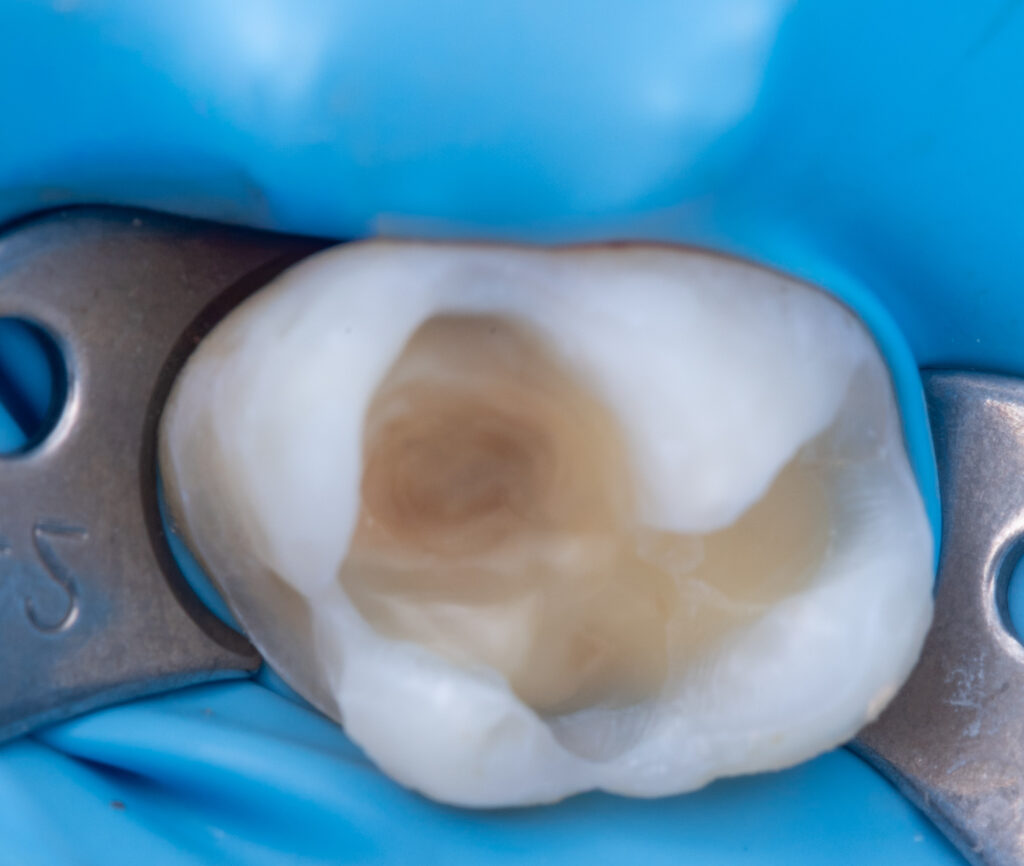

A cold test (to determine whether the tooth was vital) and a periapical X-ray were performed before treatment. The patient could open the mouth only up to two fingers wide, which created difficulties with tooth restoration and rubber dam adaptation. EverX Bulk Fill was used due to the large cavity size to help prevent fractures. The enamel surface was restored using NeoSpectra A2 and Asteria A1B.

Stain: Ice (White) / Enamel Brown.